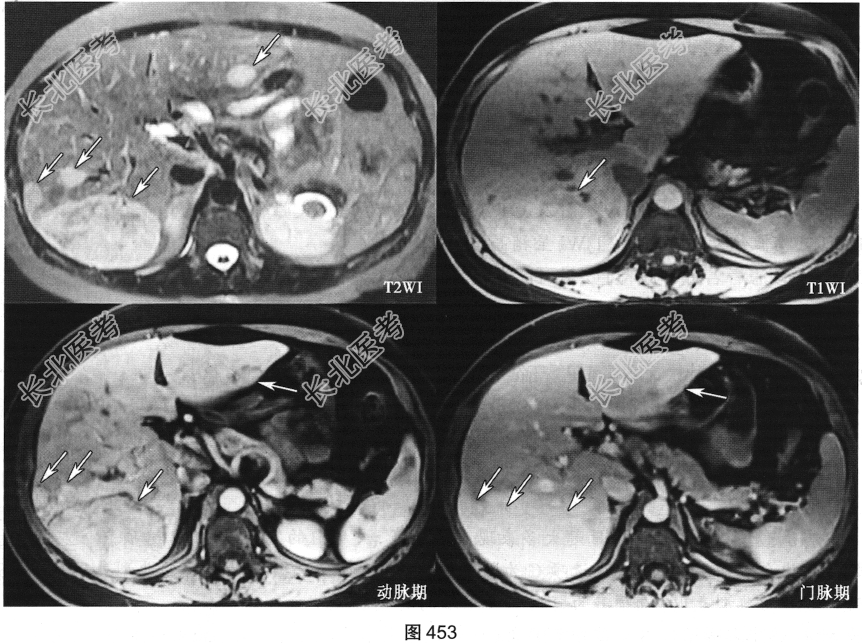

患者女性,45岁,有长期口服避孕药史,无明显不适。患者行上腹部MRI检查,如图453所示。

- 多项选择题1.依据上述资料,该患者最可能的诊断是( )

A、多发肝腺瘤

B、肝血管瘤

C、肝细胞癌

D、转移瘤

E、胆管细胞癌

F、淋巴瘤